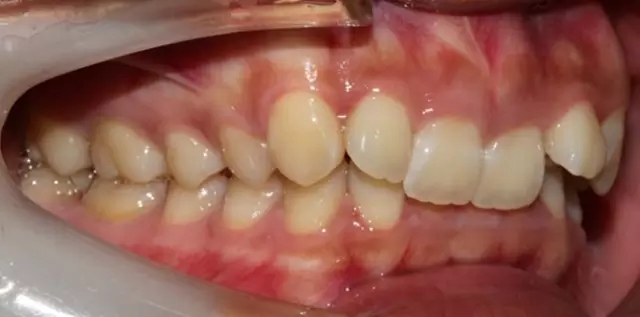

Damon 病例分享:安氏 II 類二分類露齦笑的矯治(董一磊)

治療前后對比